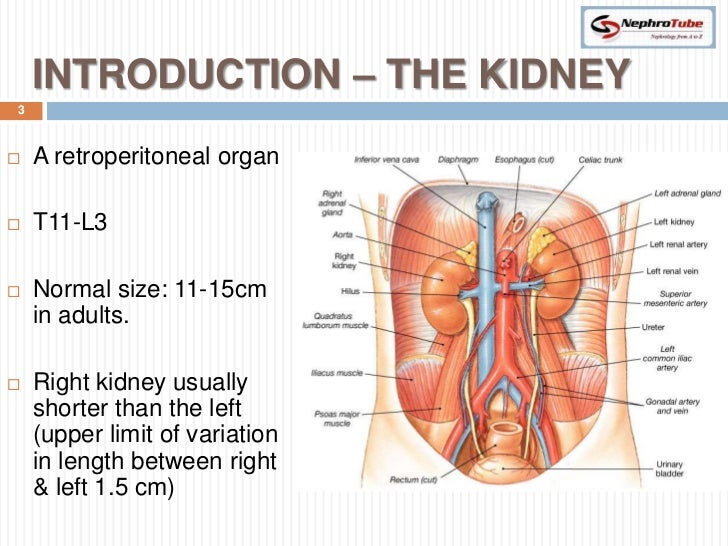

The kidneys are 11 centimeters long paired reddish brown organs situated on the posterior wall of the abdominal cavity one on each side of the vertebral column and capped by the adrenal gland. H ions are produced as a natural byproduct of the metabolism of dietary proteins and accumulate in the blood over time. Connective tissue anchors the kidneys to surrounding structures and helps maintain their normal position.

Upper portions of the kidneys are somewhat protected by the eleventh and twelfth ribs figure 1. Anatomy of the kidneys. Each kidney weighs about 125175 g in males and 115155 g in females.

Due to the presence of the liver the right kidney is slightly lower than the left kidney. They are about 1114 cm in length 6 cm wide and 4 cm thick and are directly covered by a fibrous capsule composed of dense. Anatomy of the urinary system.

The kidneys monitor and regulate the levels of hydrogen ions h and bicarbonate ions in the blood to control blood ph. Glomerular filtration glomerular filtration is the renal process whereby fluid in the blood is filtered across the capillaries of the glomerulus. The right kidney is lower than the left due to displacement by the liver.

Location of the kidneys there are two kidneys which lie retroperioneally in the lumbar area. The angiotensinconverting enzyme converts angiotensin i to angiotensin ii which stimulates the adrenal cortex to secrete aldosterone a hormone that is involved in increasing blood pressure. The basic anatomy and physiology of the kidney how kidney function changes through life the anatomy of the kidney the kidneys are comple x and beautiful organs.